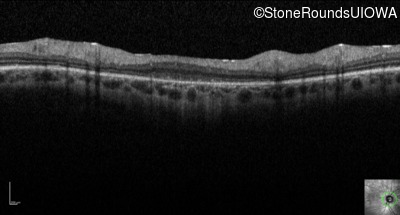

Optical Coherence Tomography - Right - 10/200

Exemplar / OCT Stack

Optical Coherence Tomography - Left - 10/160 -1